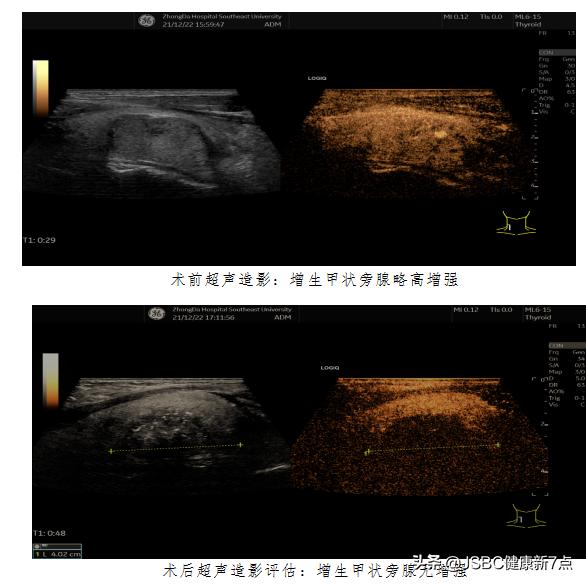

于是,揪出背后“真凶”的任务就交给了超声医学科胡中倩副主任医师。为老李做仔细的超声检查,胡中倩副主任医师发现在老李甲状腺右叶背侧中部有1枚增大的甲状旁腺瘤体,大小约3.6厘米×2.9厘米×2.2厘米。这个瘤体着实地“刁钻”,不仅体积大,更“占领”要害位置,旁边紧挨着颈总动脉、气管及喉返神经等重要组织器官,血流信号丰富。这个瘤到底是好的还是坏的呢?为明确诊断,胡中倩副主任医师等人在超声实时引导下为患者行甲状旁腺穿刺术,测瘤体内甲状旁腺激素水平并做病理学定性,最后综合诊断为甲状旁腺功能亢进症。

超声医学科胡中倩副主任医师带领高启主治医师、卢延嘉主治医师、陶敏护士等对患者在局麻下实施手术。虽是微创手术,然而老李还是有些紧张,术前消毒刚刚开始,心率达100次/分以上。于是,医生们用她们一贯的幽默与柔和的话语营造轻松的手术氛围,安慰并鼓励老李,手术过程中跟患者进行愉快地交流,缓解其紧张情绪,并实时监测患者发音有无变化,术中老李血压和心率一直保持稳定,手术成功完成。术后患者声音无改变,无喉返神经损伤,甲状旁腺激素水平术后即刻降至正常,术后一周也稳定在正常水平,血钙、血磷等检验指标也恢复正常。手术效果立竿见影,患者及家属对医院深表感激。